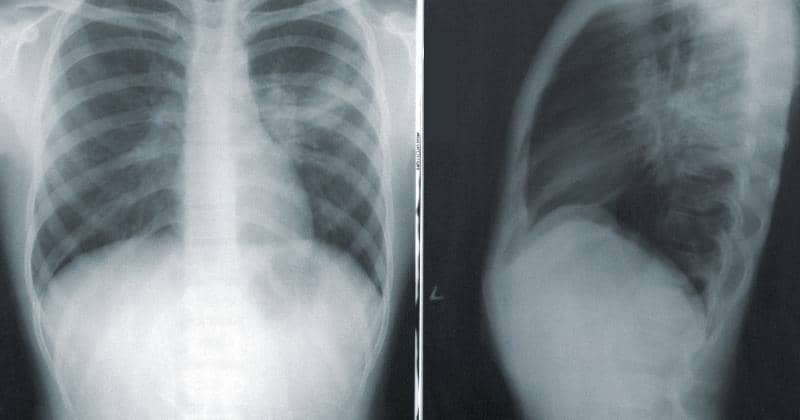

2. Deteksi dini kanker paru

Deteksi dini mejadi langkah awal yang sangat penting. Dokter Siti menjelaskan, Kemenkes terus mengupayakan deteksi dini untuk meningkatkan kualitas hidup pasien kanker paru dan menekan angka kasus kematian.

Lebih lanjut, Prof. dr. Elisna Syahruddin, Ph.D, Sp.P(K) selaku Pakar Onkologi Toraks RSUP Persahabatan dan Ketua Association Study of Thoracic Oncology menjelaskan, kini tersedia deteksi mandiri yang bisa dilakukan pasien kanker paru melalui Puskesmas.

"Ada deteksi dini yang mandiri, jadi pasiennya sendiri bisa deteksi dirinya sendiri. Kemudian, kalau dia punya risiko, dia datang ke Puskesmas, Puskesmas membuat lebih detail. Pertama, datang ke Puskesmas, Puskesmas melihat lagi jika 'iya' maka dirujuk ke dokter spesialis paru," tutur dokter Elisna.